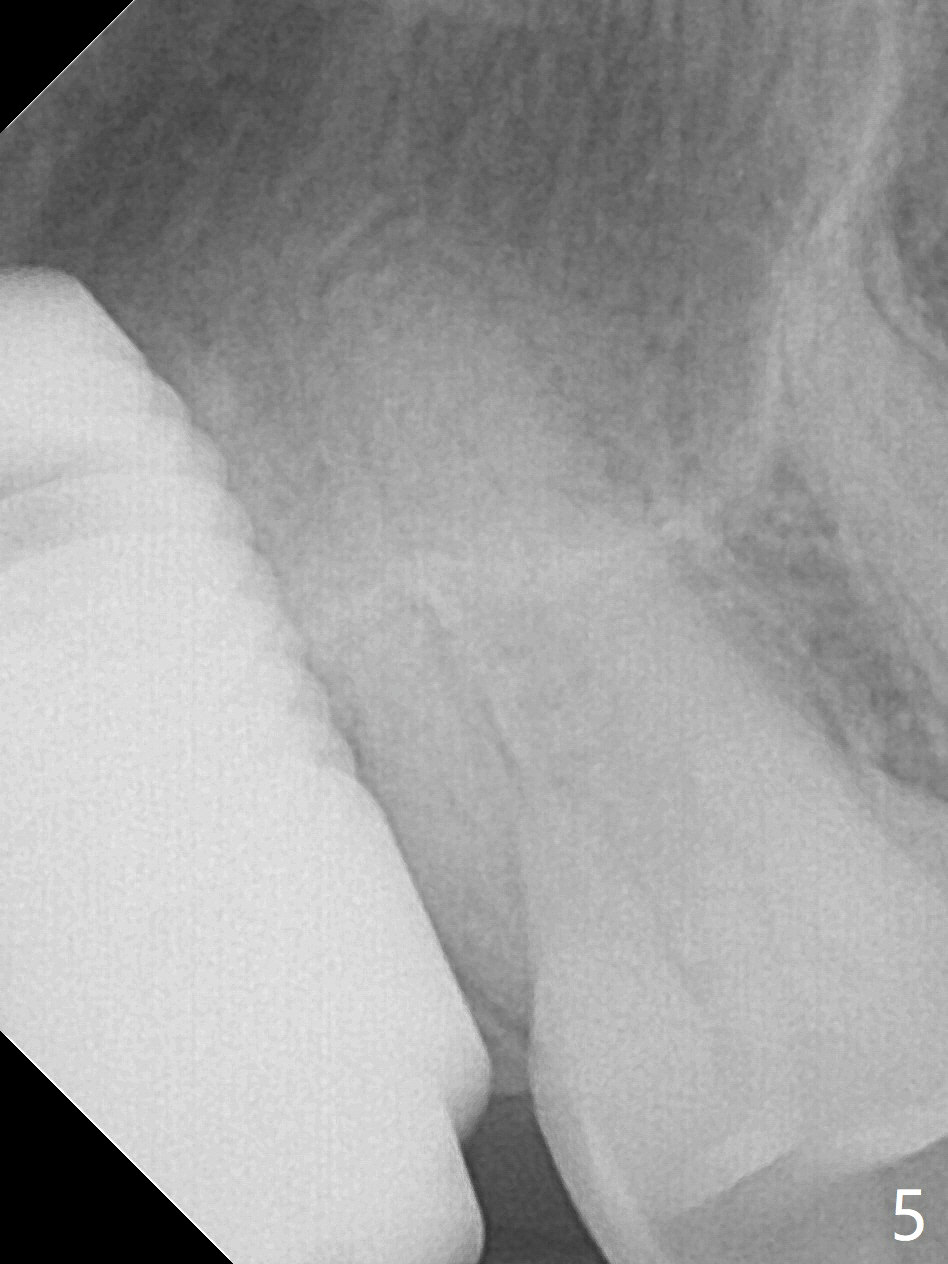

Preop exam shows that the tooth #2 has split into the buccal (Fig.1 B) and palatal (P) halves. When the tooth is extracted (Fig.2), there is a large piece of granulation tissue between these halves. The socket is large with sinus floor having pointed perforation. The latter is enlarged with rounded tapered Tatum osteotomy 2-4 mm, followed by tapered and then rounded taps. A 6.8x14 mm rounded tap has barely enough stability (Fig.3). Following placement of 2 PRF plug and 2 PRF membranes and allograft/Osteogen, a 8x17 mm cylindrical implant is placed with 60 Ncm (implant machine reading), however the implant is unstable (Fig.4). More graft is placed around the implant. With placement of 6x3 mm abutment, an immediate provisional is fabricated to close the socket. There is nasal discharge for a few days postop. PAs taken nearly 6 months postop show no bone loss (Fig.5,6). The definitive crown is cemented with access hole; there is no residual cement (Fig.7 (9 months postop)). The crown is loose 1 month post cementation (last March, Fig.8 with periimplant space (*)). The unipost was not cemented due to gag reflex. He refuses treatment immediately because of the allergy season. When he returns, spray a topical to his throat. Following crown removal, implant is found to have mobility. Panoramic X-ray (Fig.9) and CT (Fig.10,11) show fibrointegration (space) and implant intrusion into the sinus (S) without bone formation. After implant removal, the sinus floor and membrane are found to have been perforated. Osteogen plug is placed, followed by Vanilla/Osteogen (Fig.12 *) and Osteogen plug. It appears that an immediate implant is contraindicated when there is severe infection (Fig.2) with sinus floor perforation. In this case, the bone density at the upper 2nd molar is low (Fig.10 distopalatal view of 3-D image). Bone expansion and condensation is needed for implantation. Progressive loading is also necessity prior to impression.